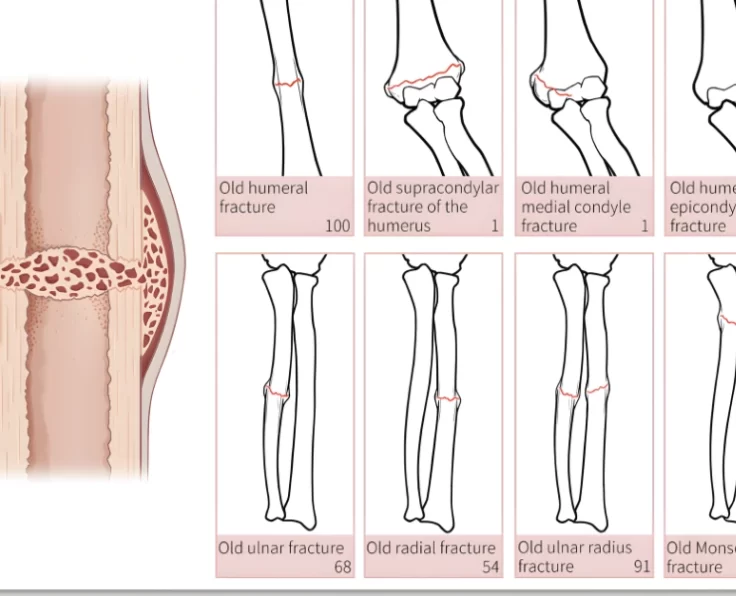

Complex Upper Limb Fractures

Fractures and dislocations of the arms and shoulders are known as upper limb fractures and dislocations.

Proximal Humeral Fractures

Proximal humeral fractures are particularly common in the elderly. A few people have axillary nerve or artery injury (which reduces sensation across the middle deltoid).

Complex Fractures in Radial Head

They account for around a third of all elbow fractures and are most common in people between the ages of 20 and 60. (with a…

A distal humerus fracture occurs when the lower end of the upper arm bone (humerus) breaks, which is one of the three bones that make…